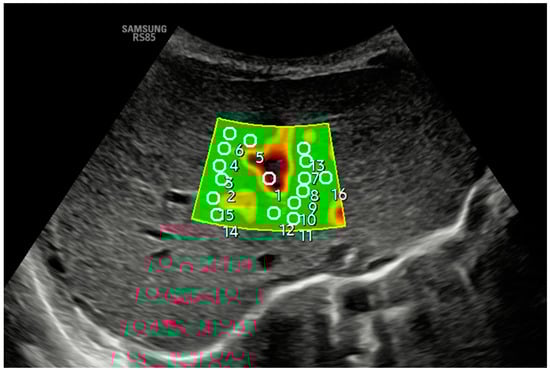

Figure 2 and Figure 3 show how 2D-SWE is performed with convex and linear probes. The measurement area is positioned with probes, generating a color map of the shear wavefront. The color map, or elastogram, can be adjusted as needed, ideally always selecting the one with the fewest artifacts. We use the smallest possible ROI and obtain at least 10–15 valid measurements within the elastogram, applying the same validity criteria as pSWE.

Figure 2.

An axial section in segment IV obtained a B-mode ultrasound image in the liver anatomical plane, and samples were acquired with 2D-SWE using a convex probe. The measurement area is positioned, and the shear wavefront color map is generated. The color map, or elastogram, can be adjusted according to the color code assigned by each commercial house from highest to lowest stiffness or, as in the example, according to the quality of the measurement (in the example, green is optimal or very optimal measure quality), always selecting the one with the fewest artifacts and using the lowest possible ROI size. At least 10–15 valid measurements are obtained within the elastogram using the same validity criteria mentioned in the main text for pSWE. In the example, ROI 1 is invalid.